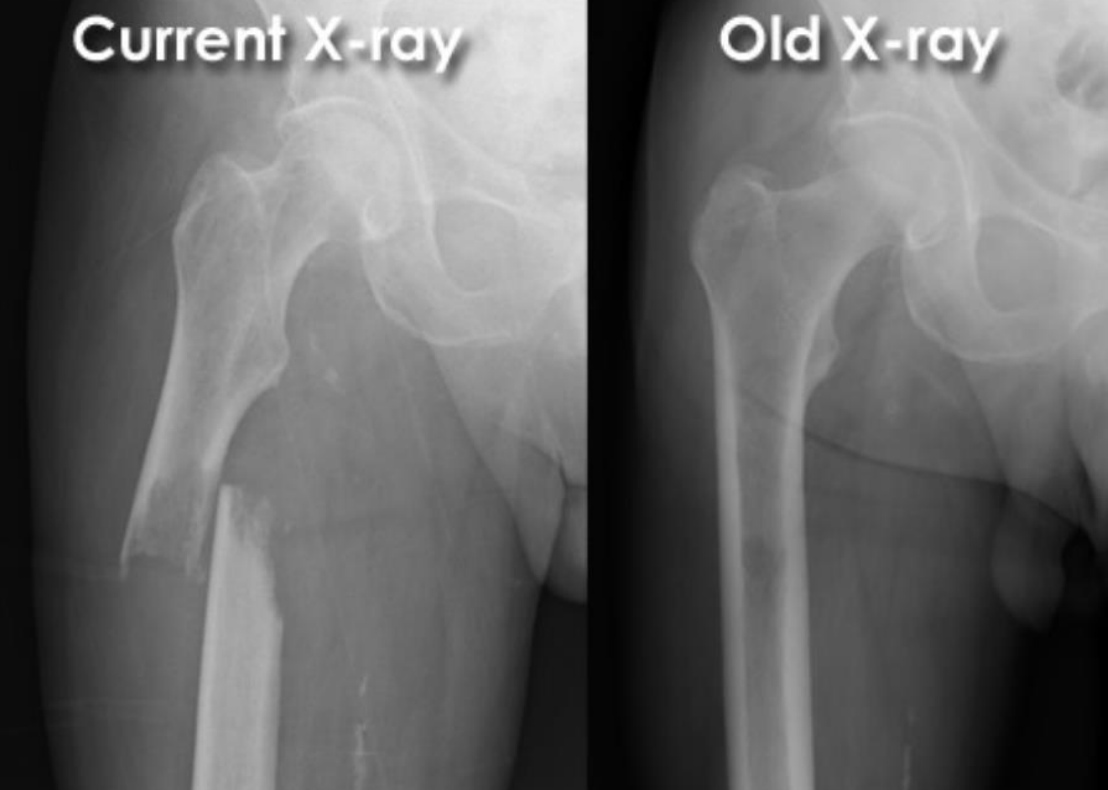

Pathological midshaft medial displaced fracture of the right femur

black spot (lower cortical density): lytic bone region

(therefore important to look at before and after fractures)

65 year old male:

fall onto left side while getting out of bed

AP radiograph of the hip

Prior DXR (bone density) scan showed marked osteoporosis

(extracapsular classification)

radiolucent intertrochanteric fracture of the left proximal femur

or

radiolucent oblique fracture through the greater trochanter and neck of the femur on the left side